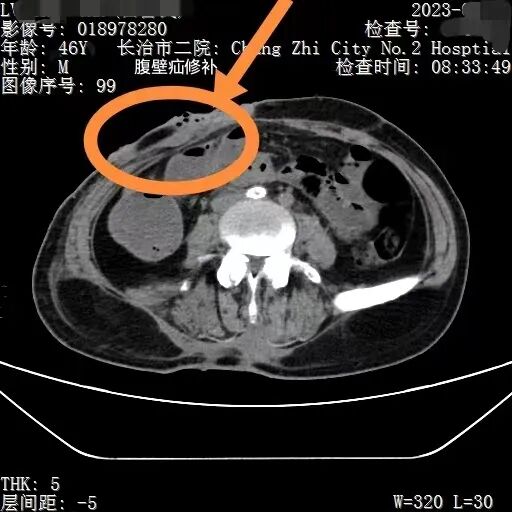

创伤性右侧腹壁疝疝出的肠管

来到市二院后,经过初步检查,吕先生被碾严重,肋骨骨折,腹壁肌肉断裂,肠管破裂,以及髋部、右臀部皮肤破裂受伤出血。CT检查中,还发现一个非常棘手的问题,右侧髂动脉与腹主动脉交界处有血肿,一旦破裂,就会有生命危险时间就是生命,普外一病区刘利亭主任当机立断,立即带领团队医护人员进入导管室,为吕先生实施侧髂动脉支架内隔绝术。在医护人员的不懈努力下,手术顺利完成。虽然拆掉了血肿这个最危险的“雷”,但吕先生的情况依然不容乐观。